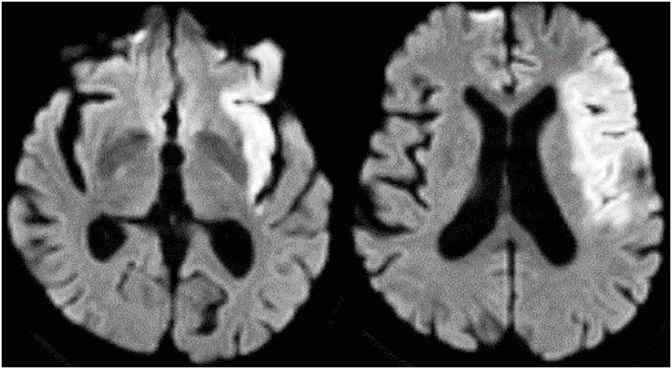

Cerebrolysin concentrate is a medication whose main active ingredient is brain-derived neurotrophic factor. It has been reported to help in the restoration of cognitive function and overall physical function after brain injuries. We present the case of a 72-year-old man with severe oral apraxia due to a left middle cerebral artery ischemic stroke involving the left insular cortex. He was being tube fed due to severe oral apraxia with cognitive decline that made it difficult for him to even imitate simple oral movements. The patient initially had impaired consciousness and cognitive function. He also had limited physical activity due to acute stroke complications, such as hemorrhagic transformation of cerebral infarction, and required bed rest until 23 days after onset. The patient received intravenous cerebrolysin concentrate in addition to intensive rehabilitation therapy from 23 days after onset. After rehabilitation and administration of cerebrolysin concentrate, there was a marked recovery within a short period of time to the point where oral intake of a regular diet was possible, indicating a significant improvement in oral apraxia. It is a notable example of the potential therapeutic effect of cerebrolysin concentrate for post-stroke oral apraxia.